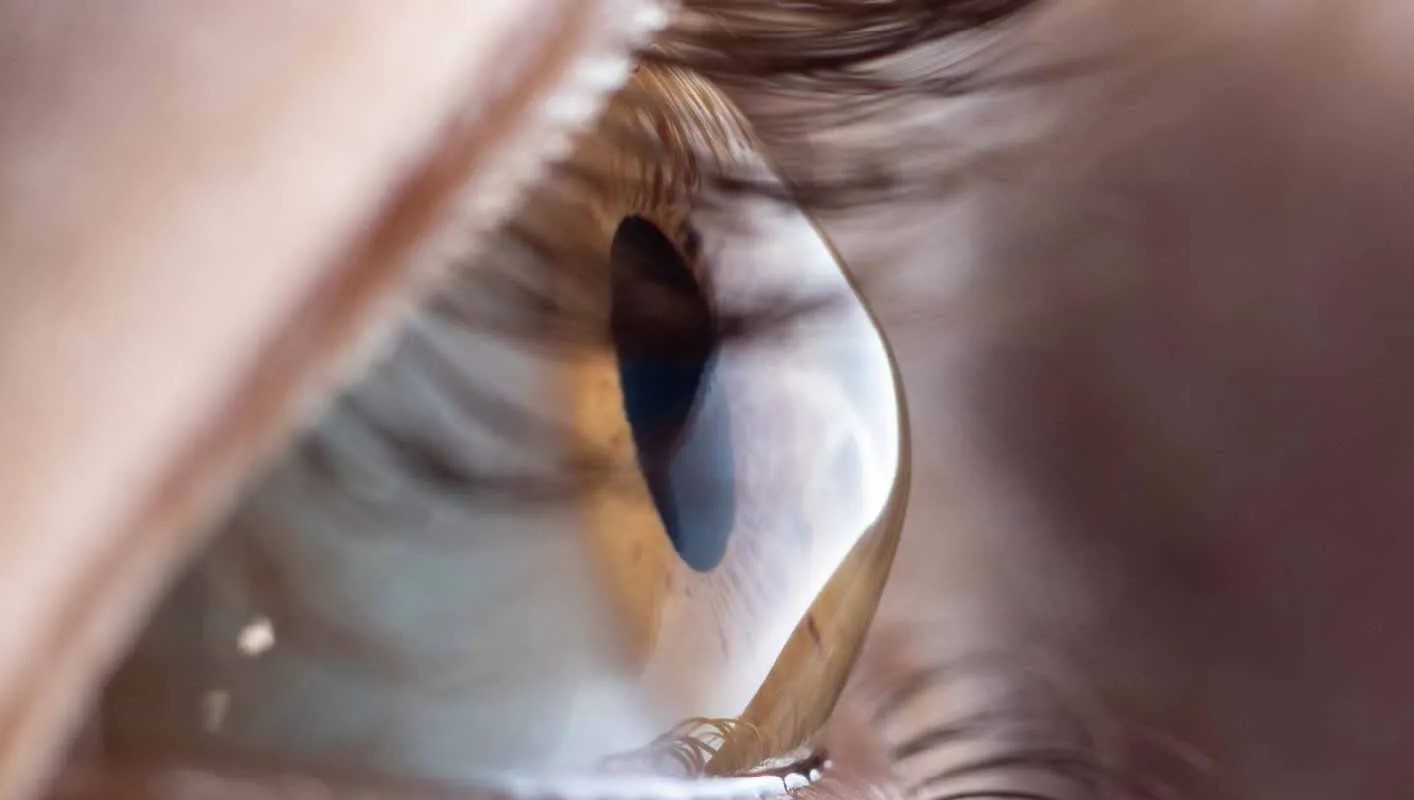

Ο κερατόκωνος, ICD-10 H18.6, είναι μία οφθαλμική νόσος που αφορά και περιγράφει το σχήμα ή καλύτερα την καμπυλότητα του κερατοειδούς χιτώνα, του διάφανου, δηλαδή τμήματος της οφθαλμικής επιφάνειας που συναντούν οι ακτίνες του φωτός μπαίνοντας στο μάτι. Η επιφάνεια του κερατοειδή, λοιπόν, λαμβάνει “κωνική” μορφή, προκαλώντας έτσι “παραμόρφωση” του οπτικού ειδώλου που δεν μπορεί να εστιαστεί πάνω στους φωτοϋποδοχείς του ματιού που βρίσκονται μέσα στο μάτι. Παράλληλα αρχικά παρατηρείται λέπτυνση του κερατοειδούς και αργότερα και θολερότητα στην περιοχή της βλάβης.

Η φυσική εξέταση δε δίνει πάντοτε στοιχεία για μια σίγουρη διάγνωση. Ωστόσο η κερατομετρία μπορεί να δώσει αλλοιωμένες παραμέτρους. Σε πιο προχωρημένα στάδια η διάγνωση είναι πιο εύκολη και με τη βοήθεια της σχισμοειδούς λυχνίας ο κερατοειδής εμφανίζει τη γνωστή κωνική μορφή καθώς και λέπτυνση και θόλωση της κεντρικής περιοχής του.